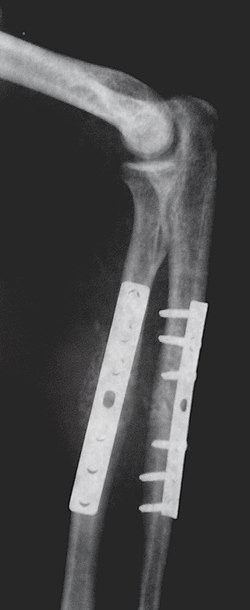

요골과 척골 골절을 치료하기 위한 정형외과 임플란트. 척골의 눈에 띄는 골절을 확인하세요. (오른쪽 아래팔)